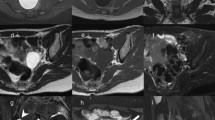

Krukenberg tumour from gastric carcinoma in a 23-year-old woman. (a) Sagittal, (b) axial and (c) coronal T2-weighted images show a heterogeneous mass characterized by solid components with low signal intensity (white arrows) and cystic components with high signal intensity (white arrowheads). (d) Sagittal contrast-enhanced fat-suppressed T1-weighted image demonstrates enhancement of the solid components (white arrow). (e) Axial DW image (b = 800 s/mm2) demonstrates increased signal of the solid components of the lesion indicating hypercellularity. (f) Photomicrograph (H&E X200) shows ovarian parenchyma diffusely infiltrated by signet-ring cells

Serous papillary carcinoma in a 48-year-old woman. (a) Axial, (b) sagittal and (c) coronal T2-weighted image show a cystic and solid mass (white arrows). (d) Axial contrast-enhanced fat-suppressed T1-weighted image shows the enhancing exophytic papillary projections of the tumour (white arrow). (e) Axial DW image (b = 800 s/mm2) demonstrates increased signal of the lesion (white arrow), indicating hypercellularity

Mucinous cystadenocarcinoma in a 57-year-old woman. (a) Axial, (b) coronal and (c) sagittal T2-weighted images show a large mass with mixed solid and multilocular cystic appearance with low signal intensity of the solid component and variable signal intensity within the locules (“stained glass appearance”). (d) Axial, (e) coronal and (f) sagittal contrast-enhanced fat-suppressed T1-weighted images demonstrate marked enhancement of the solid component, wall and septa of the tumour

Peritoneal carcinomatosis due to disseminated ovarian papillary serous cystadenocarcinoma in a 63-year-old woman. (a) Axial T2-weighted, (b) coronal T2-weighted, (c) axial T1-weighted, (d) coronal T1-weighted images show multiple tumour implants in the left paracolic gutter (white arrows) and omental implants (white arrowheads in a, c). (e) Photomicrograph (H&E X200) shows solid and papillary structures invading omental adipose tissue

Endometrioid and clear cell tumours are commonly associated with endometriosis. These tumours usually appear as complex masses with solid and cystic components, although they can also be predominantly cystic (Figs. 13 and 14) [39]. However, the rapid growth of an endometrioma, along with multilocularity and presence of mural nodules within the haemorrhagic cyst with enhancement after gadolinium administration should raise the suspicion of malignancy [32, 40].

Endometrioid adenocarcinoma in a 57-year-old woman. (a) Axial and (b) coronal T2-weighted images show complex masses with solid (white arrowheads) and cystic (white arrows) components. On (c) axial fat-suppressed T1-weighted image, the cystic component shows haemorrhagic hyperintense signal (white arrow). On (d) axial contrast-enhanced fat-suppressed T1-weighted image, the solid component shows marked enhancement (white arrowhead). (e) Photomicrograph (H&E X20) shows capsular invasion by neoplastic glands

Endometrioid adenocarcinoma in a 60-year-old woman. (a) Coronal and (b) sagittal T2-weighted images show a predominantly cystic mass with solid component arising from the inferior wall (white arrowheads). (c) Axial fat-suppressed T1-weighted image shows hyperintense haemorrhagic content of the cyst (*) and solid parietal component (white arrowhead). (d) Axial DW image (b = 800 s/mm2) demonstrates increased signal of the solid component of the lesion (white arrowhead) indicating hypercellularity. (e) Photomicrograph (H&E X300) shows neoplastic glands cystically dilated

Yolk sac tumour, also known as endodermal sinus tumour, is relatively rare and is responsible for about 1 % of ovarian malignancies. This tumour generally presents in the second or third decade as a large mixed cystic and solid mass with the bright dot sign, namely foci of enhancement due to dilated vessels (small aneurisms) as a result of increased vascularity [41]. It is not uncommon to find haemorrhagic areas with high signal intensity on T1-weighted images (Fig. 15).

Yolk sac tumour in a 26-year-old woman. (a) Sagittal and (b) axial T2-weighted images show a mixed cystic and solid mass (white arrows). (c) Axial T1-weighted image shows haemorrhagic areas with high signal intensity within the lesion (white arrowhead). (d) Sagittal and (e) axial contrast-enhanced fat-suppressed T1-weighted images show marked enhancement of the solid component (white arrows). Peritoneal fluid can also be seen (* in a, b). (f) Photomicrograph (H&E X200) shows endodermal sinus pattern with Schiller-Duval bodies; these structures are covered by tumour cells and has a central capillary